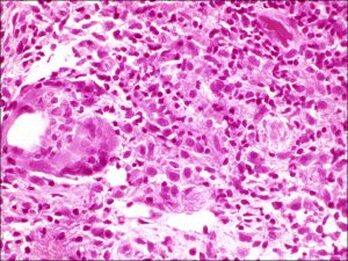

natural history of a chalazion.The initial inciting factor is blockage of a Meibomian gland. This causes the sebaceous material that is within the meibomian gland to expand. This results in a painless swelling, which is called a chalazion. Initially, the lesions are painless and expand slowly. Local tenderness occurs when there is spread of the sebaceous material to the surrounding tissues leading to local inflammation, or if there is a secondary infection which results in increased tenderness. Untreated, chalazia can increase in size and become quite firm although most will burst through to the surface (skin) or through the conjunctiva and will resolve slowly but surely. Chalazia may occur in childhood and in adults, often in the 30 - 50 age group. Predisposing factors include conditions like underlying blepharitis and acne rosacea. The use of makeup and the wearing of contact lenses does not increase the incidence of chalazia. Recently, with Covid, it has become apparent that the wearing of masks may lead to a drying effect on the eyelid margins with secondary blockage of the Meibomian glands. We have seen a significant increase in the incidence of chalazia during the Covid years 2020-2023. A large chalazion on the upper eyelid may cause a mechanical ptosis. The change in the curvature of the eyelid and also the pressure on the cornea can make it difficult to wear contact lenses. Lower eyelid chalazia can result in an ectropion with resultant epiphora (tearing). Secondary calcification may develop in the presence of chronic chalazia. Malignant transformation is extremely rare. external hordeolum A chalazion that is showing anteriorly through the skin with the appearance of a barley corn: it was therefore described as an external hordeolum. These lesions can be drained anteriorly. If they are firm, injection with steroids is reasonable. Even though they look dramatic, once they heal, the eyelid does not show any residual scarring Infections of the glands of Zeis are called styes or external hordeolum. These sebaceous oil glands open into the eyelash follicles. The term external hordeolum has erroneously been used for a chalazion that becomes infected and erodes through the skin. what are meibomian glands?Meibomian glands ae glands within the tarsus of the upper and lower eyelids. There are 30 glands in the upper eyelid and about 25 glands in the lower eyelid. They are also called tarsal glands. Meibomian glands produce an oily substance called meibum which is important in reducing the evaporation rate of tears in our tear film. These are exocrine glands: they have ducts that secrete their contents via ducts that open at the eyelid margin. They are also holocrine glands because the secretions result from lysis of the secretory glands, which causes them to release the oily substance into the Meibomian duct. Meibum not only reduces evaporation of the aqueous component of the tear film, but it also keeps the aqueous component from spilling over the edge of the eyelid by forming a film on the tear film and at the edge of the eyelid. Meibum further assists in allowing the eyelids to shut in an airtight manner. Meibomian glands: etymologyHeinrich Meibom (1638 - 1700) was a German physician who studied in France, Germany, Italy and England. He went on to become a Professor of Medicine and also a Professor of History and Poetry. He wrote Latin poetry for which he was well known. differential diagnosis of a chalazionStye Adenocarcinoma Sebaceous Gland Carcinoma Nodular basal cell carcinoma Schwannoma This patient has a stye which is the lesion close to the eyelid margin and originates from the lash root and a chalazion which is the lower lesion. There is also a small inclusional cyst supero-medially on the upper eyelid and a seborrheic keratosis on the lateral nasal wall. There are also multiple small papillomas Histopathology of chalaziaHistopathology of the contents of a chalazion reveals a lipogranulomatous reaction with multinucleated giant cells, foamy macrophages, plasma cell, neutrophils and lymphocytes with lipid vacuoles. Histopathology will show areas of clear spaces which do not stain with H&E staining because these are lipid droplets. Older lesions may manifest fibrosis Histopathology courtesy of Prof. Nick Mamalis MD, MoranCore how do you manage chalazia presenting acutely?Patients may present with a non-tender bump on the upper or lower eyelid, in which case the lesion may cause distortion of the cornea which affects vision or may be cosmetically unacceptable. Larger lesions can cause pressure on the cornea with resultant astigmatism. Central chalazia can be in the line of sight and can also cause a mechanical ptosis interfering with the field of vision. Management: